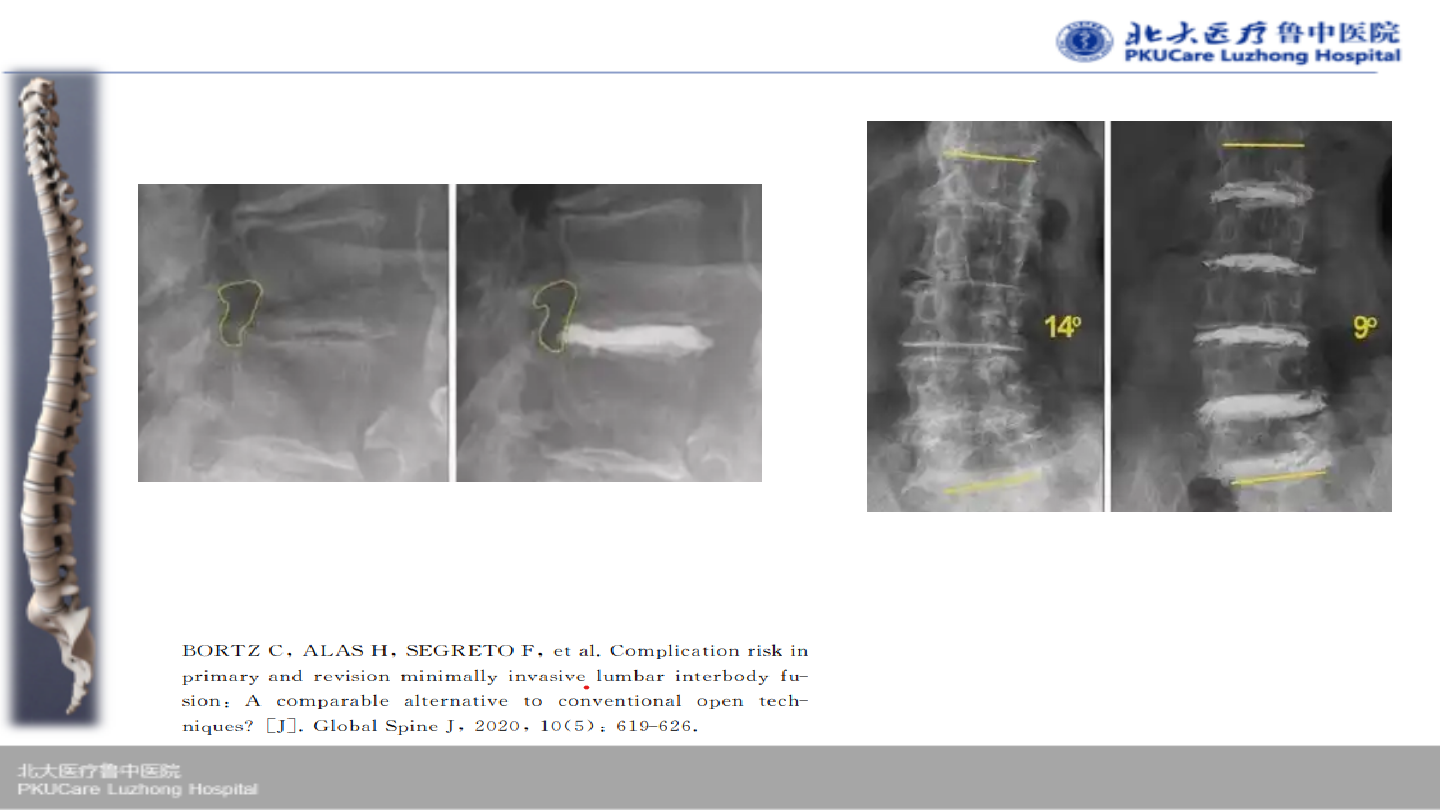

方案:

经皮骨水泥椎间盘成形术

(percutaneous cement discoplasty

PCD)

P.P. Varga

教授